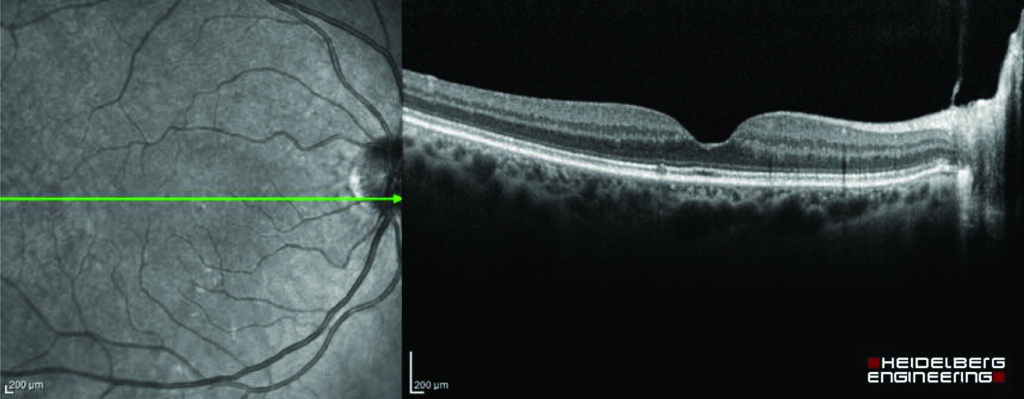

A scan is a visual way of viewing and measuring the inner layers of your eye. The scans can diagnose conditions that are not visible on the surface of the eye and can help to monitor the progression and treatment of the condition.

OCT (optical coherence tomography) scans are the most common types of scans, but you may also have other scans while visiting the eye clinic. All the scans are painless and non-invasive, although we may need to gently lift up your eye lids. The scans only take a couple of minutes.